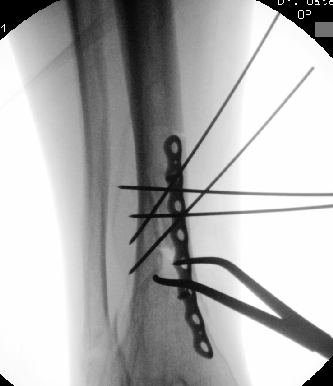

Midshaft #clavicle nonunion prediction at 6 wks post-injury appears superior to time of injury. We found 3 simple clinical predictors can accurately predict #fracture healing in most cases. This months @jbjs / jbjs.org/issue.php from our unit @EdinburghTrauma